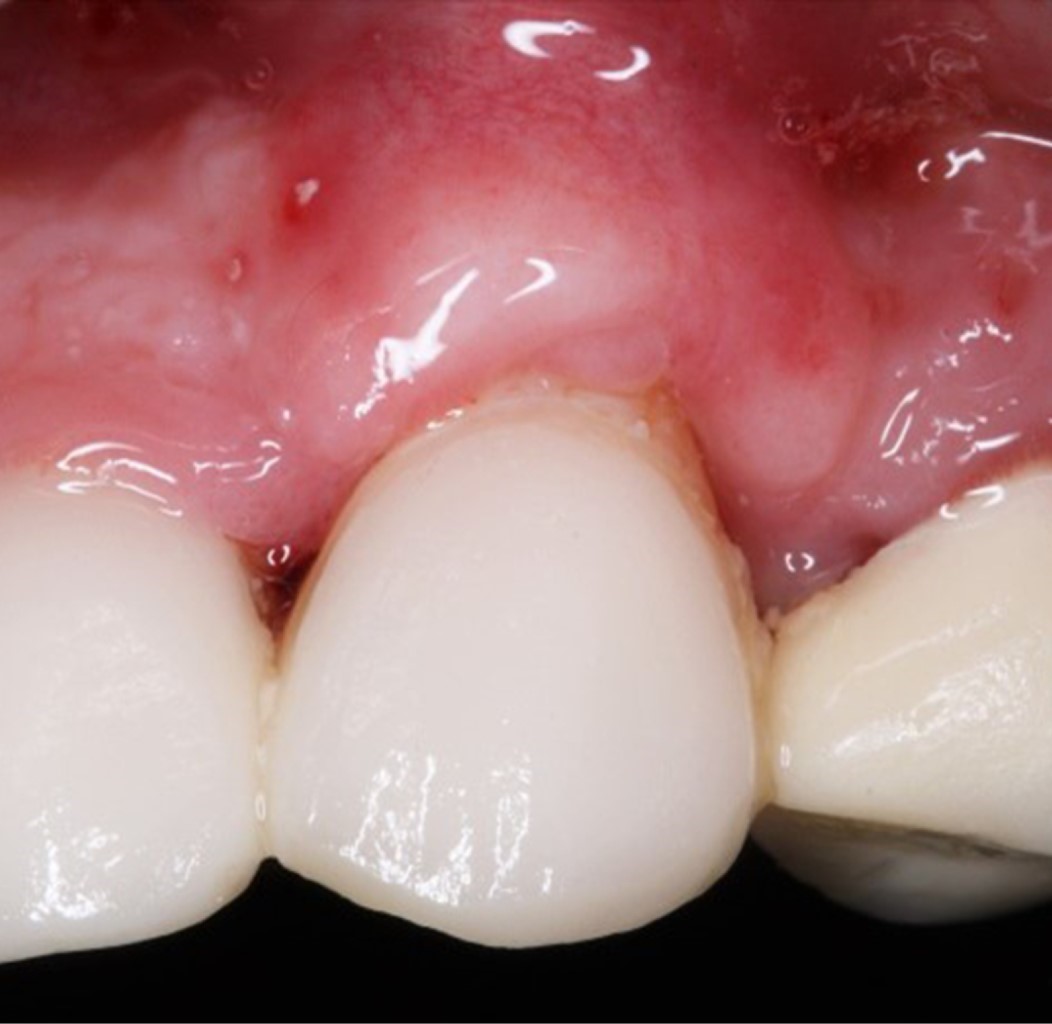

Las suturas palatinas fueron retiradas a los siete días. En el sitio de la cobertura radicular, las suturas fueron removidas a los 14 días (Figura 8). Se dio seguimiento al paciente a los siete, 14 y 30 días, hasta los seis meses para valoración final, donde se observa cobertura radicular completa (100%), cambio de fenotipo gingival mediante el aumento de tejido queratinizado, mejora en la estética y reducción total de la sensibilidad dental (Figura 9).